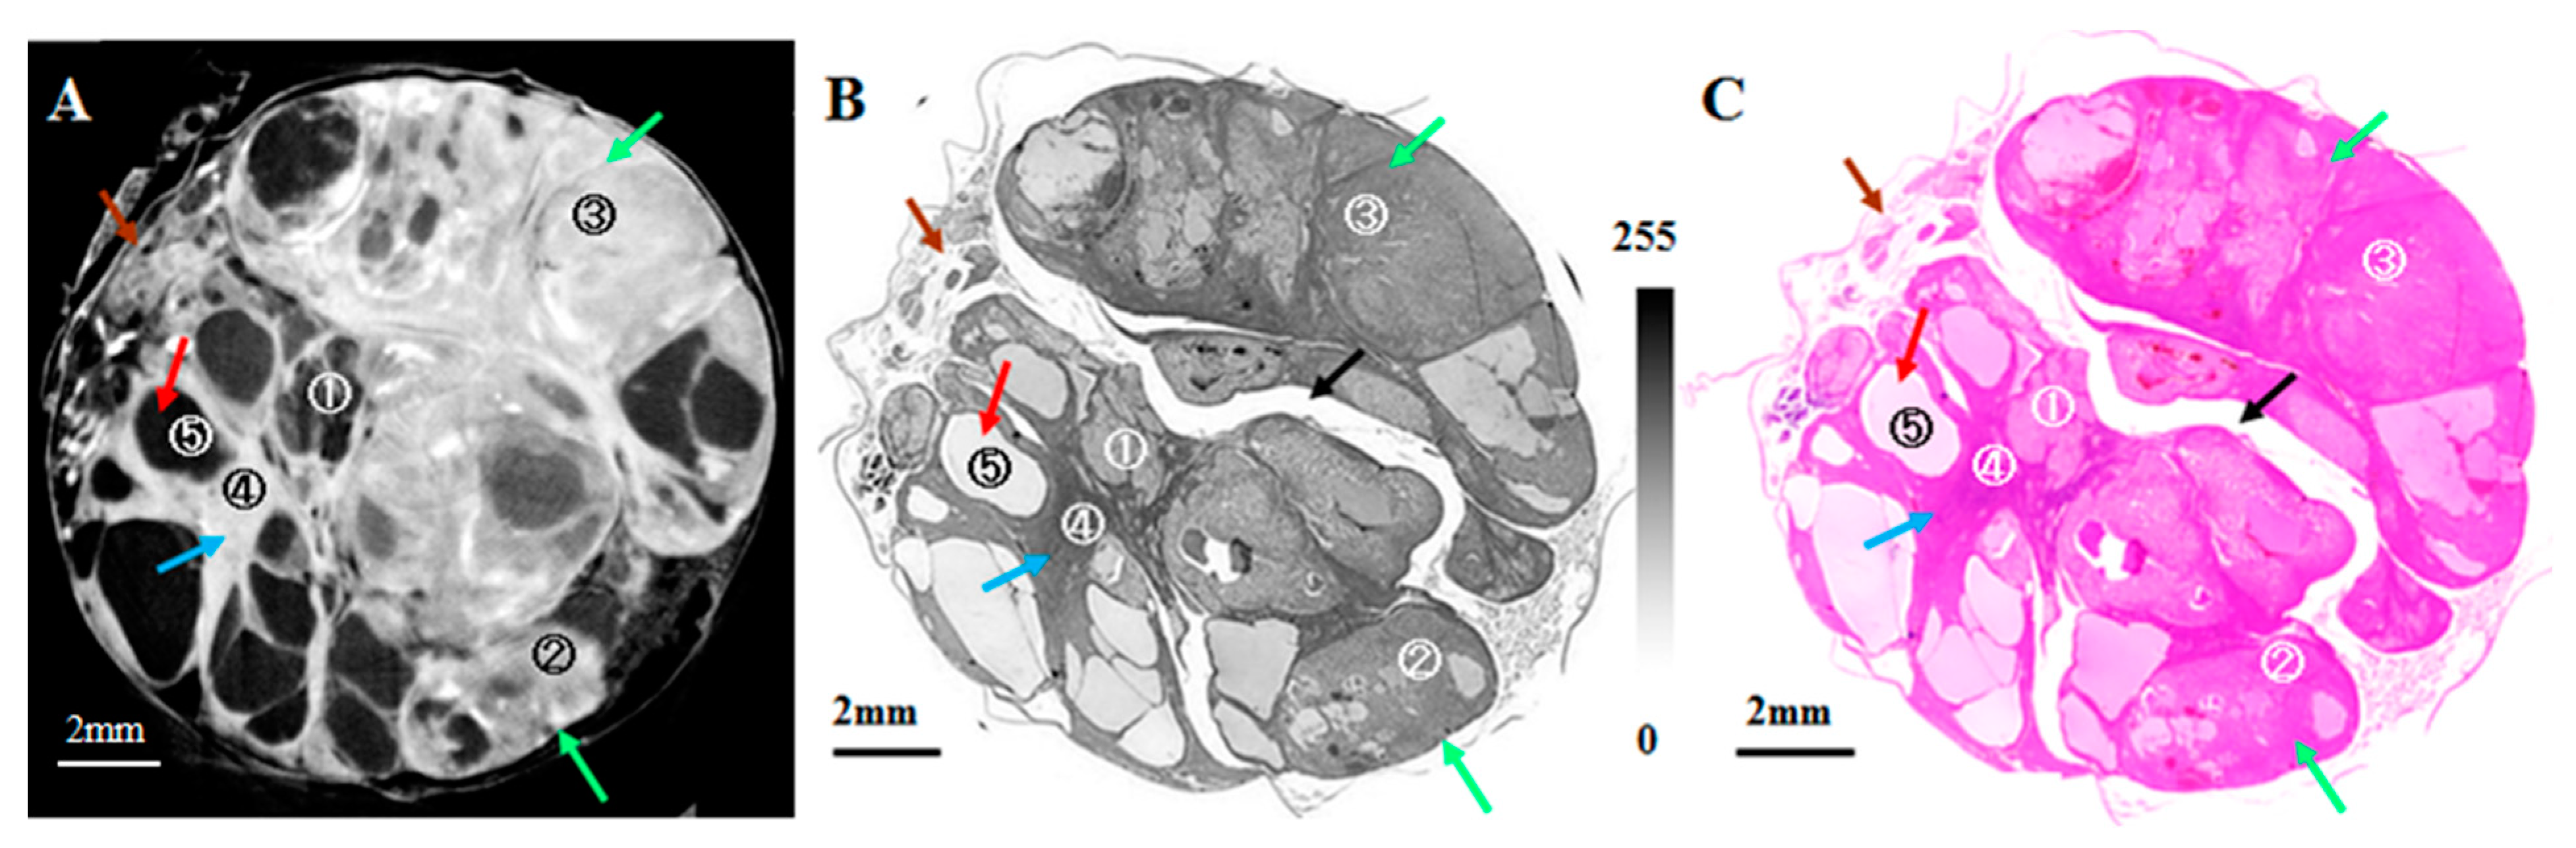

- Takeda, T.; Wu, J.; Lwin, T.T.; Yoneyama, A.; Hyodo, K.; Matsuda, Y.; Kose, K. Interferometer-based phase-contrast X-ray computed tomography of colon cancer specimens: Comparative study with 4.74-T magnetic resonance imaging and optical microscopy. J. Comput. Assist. Tomogr. 2007, 31, 214–217. [Google Scholar] [CrossRef]

- Thet Thet, L.; Yoneyama, A.; Imai, M.; Maruyama, H.; Hyodo, K.; Takeda, T. Testicular seminoma in the aged rat visualized by phase-contrast X-ray computed tomography. Acta Radiol. Open 2018, 7, 205846011880665. [Google Scholar] [CrossRef]

- Lwin, T.T.; Yoneyama, A.; Maruyama, H.; Takeda, T. Visualization Ability of Phase-Contrast Synchrotron-Based X-ray Imaging Using an X-ray Interferometer in Soft Tissue Tumors. Technol. Cancer Res. Treat. 2021, 20, 15330338211010121. [Google Scholar] [CrossRef]